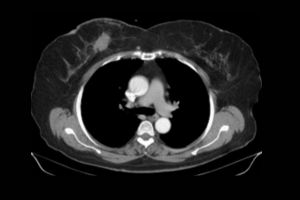

What is a CT Head and Left Orbit scan?

A CT Head and Left Orbit scan is a specialised imaging test that uses computed tomography (CT) technology to produce detailed cross-sectional images of the head and the left eye socket (orbit). This scan helps evaluate the bones, brain, soft tissues, and structures within and around the left eye. It is commonly used to detect abnormalities such as fractures, tumours, infections, bleeding, or foreign bodies in specified areas. The test is non-invasive and may involve the use of a contrast agent to enhance the visualisation of blood vessels and specific tissues. It is often ordered in cases of trauma, neurological symptoms, or eye-related concerns.

- To identify tumours, masses, or cysts in the brain or eye socket.

- To evaluate for bleeding, swelling, or ischemia in the brain.

What can CT Head and Left Orbit detect?

A CT Head and Left Orbit can detect fractures, tumours, infections, bleeding, and other abnormalities in the brain, skull, and eye socket.